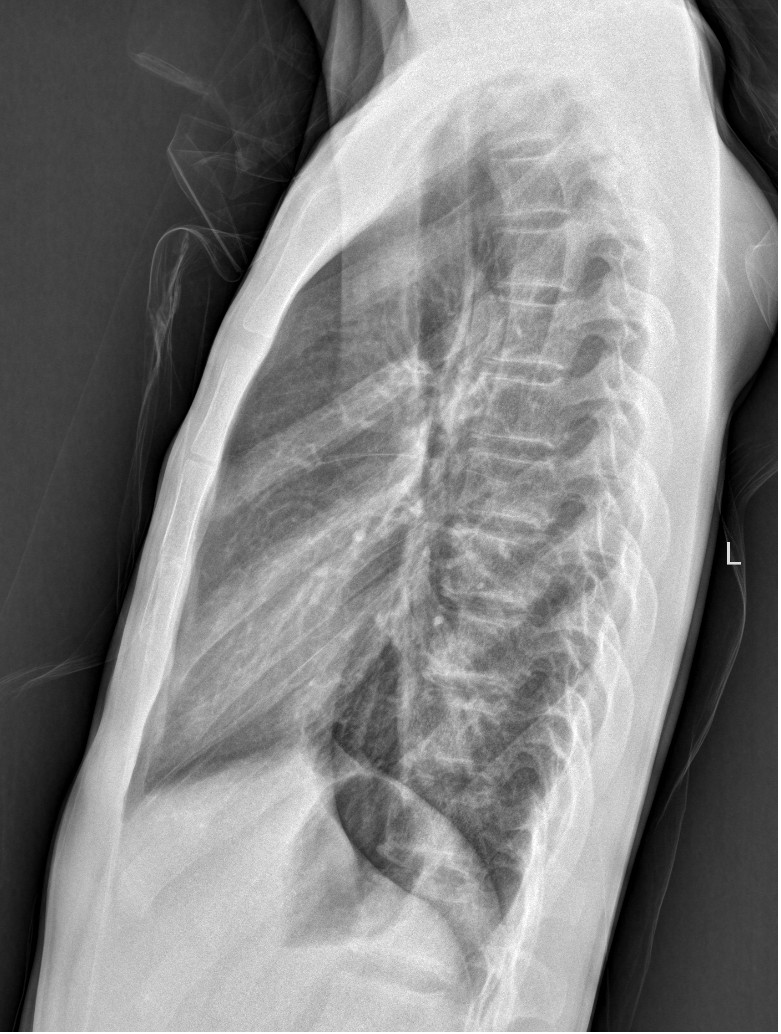

DR是最常用的X线检查技术,它是利用X射线的穿透能力生成从黑到白不同灰度的影像,也就是大家常说的“拍片”。

缺点:只能提供二维的平面影像,组织前后重叠且密度分辨率低,有些部位是看不见的,若需进一步观察,需要进行升级版的CT检查。

我们可以把人体组织想象成一块面包,DR检查是把面包压扁了来看。当X线穿过人体后,遇到被遮挡的部位,图像上是不会显示的。就像一片面包,看不到里面的纤维纹理,但是它的结构完整性更强。

DR和CT是两种不同的检查方法,其侧重点不同,各具优势,两者不能互相替代。比如对于骨折来说,DR诊断要比CT更好,因为DR可以直接排除绝大多数的骨折,但是对于隐形性的骨折,CT会更好一些,可以作为DR检查后的进一步定性检查方法。